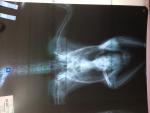

Сделали рентген, Остеоартроз коленных суставов.

Какаду, более 10лет. Сделали рентген, врач сказал., что у нас признаки остеоартроза коленных суставов, эпифизарный остопароз (может неправильно написала, почерк не разобрать).

Неплохо бы сами рентген-снимки увидеть.

Уже проявившия остеопароз не лечится. Максимум- немножко корректируется, и создаются условия для его "неразвития",и исключения травм.

Подробно- описание содержания и кормления птицы. ЕЩЕ РАЗ РЕНТГЕН-четкий, с хорошо разложенной птицей. Для исключения(или подтверждения) старых травм.